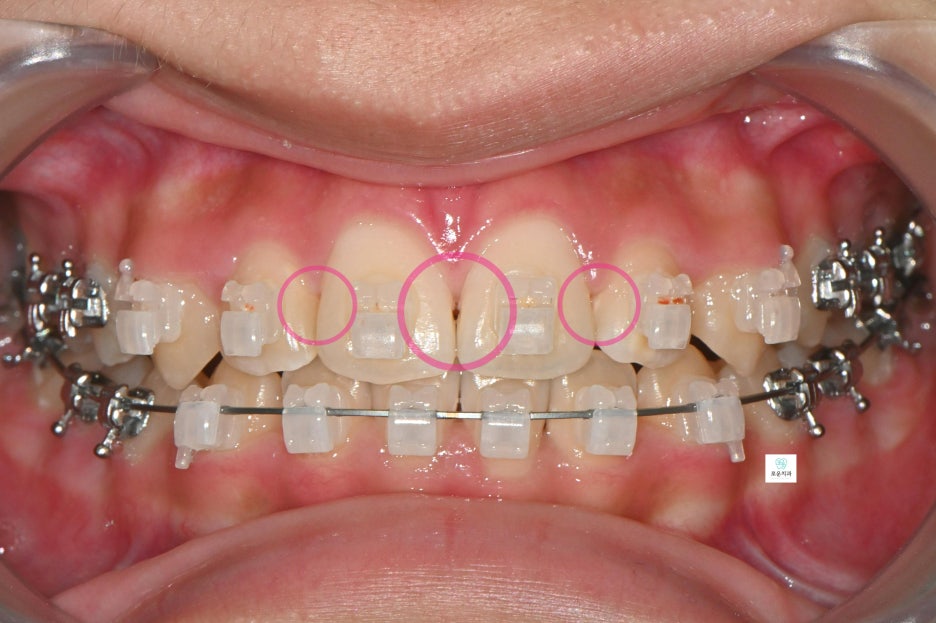

“교정 중 발생한 앞니 사이 충치 치료 사례”

장기간 교정 치료를 진행 중이던 환자분으로

앞니 사이 충치가 발견되어 치료를 위해

내원하셨습니다.

앞니에 생긴 우식은 치아 4개에 사이에 생겨 총 6면의 우식이 발생

→ 치아는 붙어 있는 면 양쪽으로 우식 진행되기 때문에 면수로 진행

첫 방문에서는 검진을 통해

치료 부위를 확인하였고,

두 번째 방문에서는 교정치과와 일정 조율 후

와이어를 제거한 상태로 내원하여

치료를 진행했습니다.